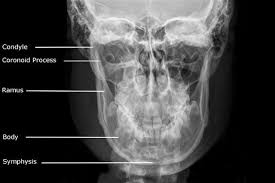

Radiographic Anatomy Of Facial Bones And Mandible Facial Bones Radiology Anatomy